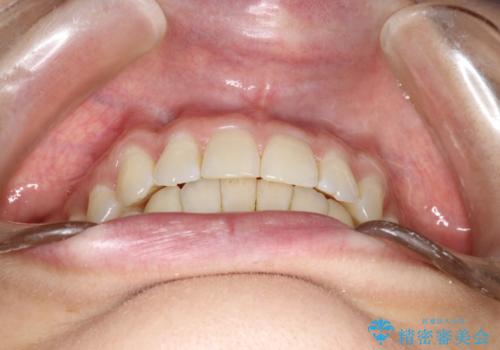

前歯のガタガタをインビザラインで矯正

- 前歯のがたつきを気にされて来院されました。

右上の前から2番目の歯が前方に大きく傾いており、下の前歯もガタガタしていました。

しっかりとマウスピースを使用していただけたので、順調に治療を終えることができました